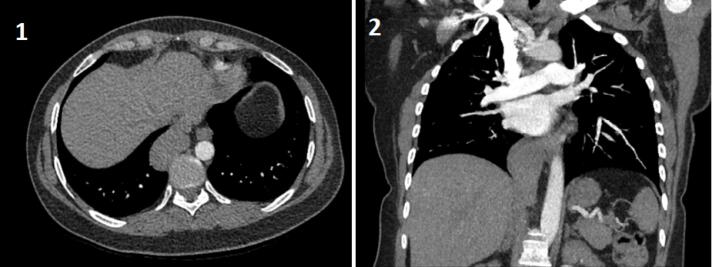

We present a case with an intrathoracic caudate lobe in a 45-year-old woman who referred with a complaint of nonspecific chest pain. She denied previous history of trauma or surgery. Computed tomography (CT) pulmonary angiography showed a paravertebral, soft tissue mass which raised suspicion of a pleural tumor. In the coronal plane, the mass was protruding to the abdomen and had similar density with liver. Magnetic resonance imaging confirmed the diagnosis.

我们提出一个病例与胸内尾状叶在一个45岁的妇女谁提到投诉非特异性胸痛。她否认有外伤或手术史。CT肺血管造影显示椎旁软组织肿块,怀疑为胸膜肿瘤。在冠状面,肿块向腹部突出,密度与肝脏相近。磁共振成像证实了诊断。